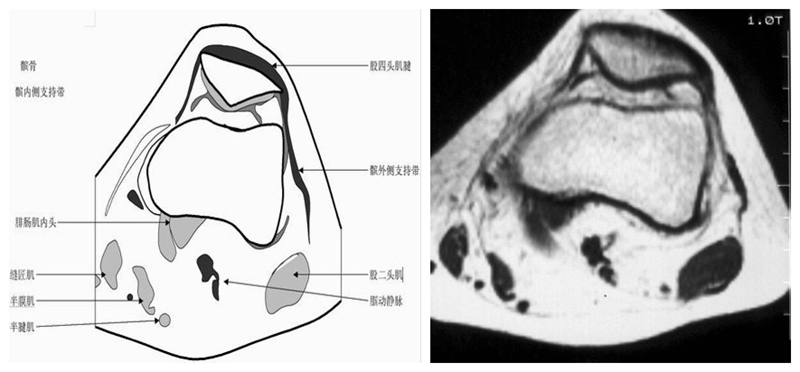

膝关节横断面MRI解剖

三维影像首选的方位,便于与CT比较,可准确地展现髌骨内外侧关节面。

横断面解剖第三层

横断面解剖第四层